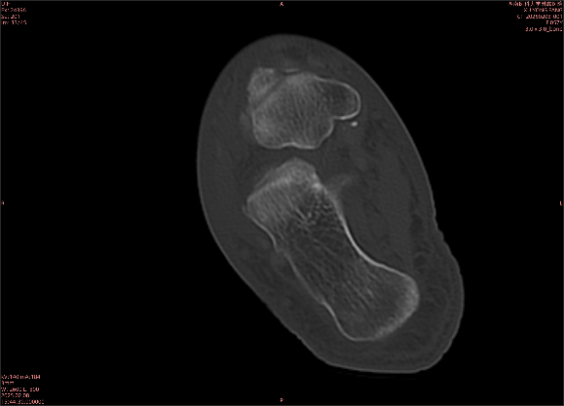

舉例圖像

圖1

圖2

專業(yè)解釋看不懂沒關系,大家看圖1和圖2就可以了,這是同一個患者跟骨的磁共振和CT圖像,圖1的紅色箭頭指示的黑線就是磁共振圖像顯示的骨折線,一目了然。而對比圖2的CT圖像上并未顯示異常。